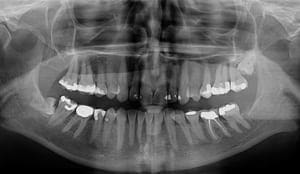

Digitale bilder

Røntgen har lenge vært et viktig verktøy for å kunne oppdage skader i tenner og kjeveben. Men det er ikke alt vi kan se på røntgen.

Digitalt røntgen

Ved hjelp av moderne teknologi som digitalt røntgen og digitalt foto finnes det i dag helt andre muligheter for å involvere pasienten i sin egen tannhelse.